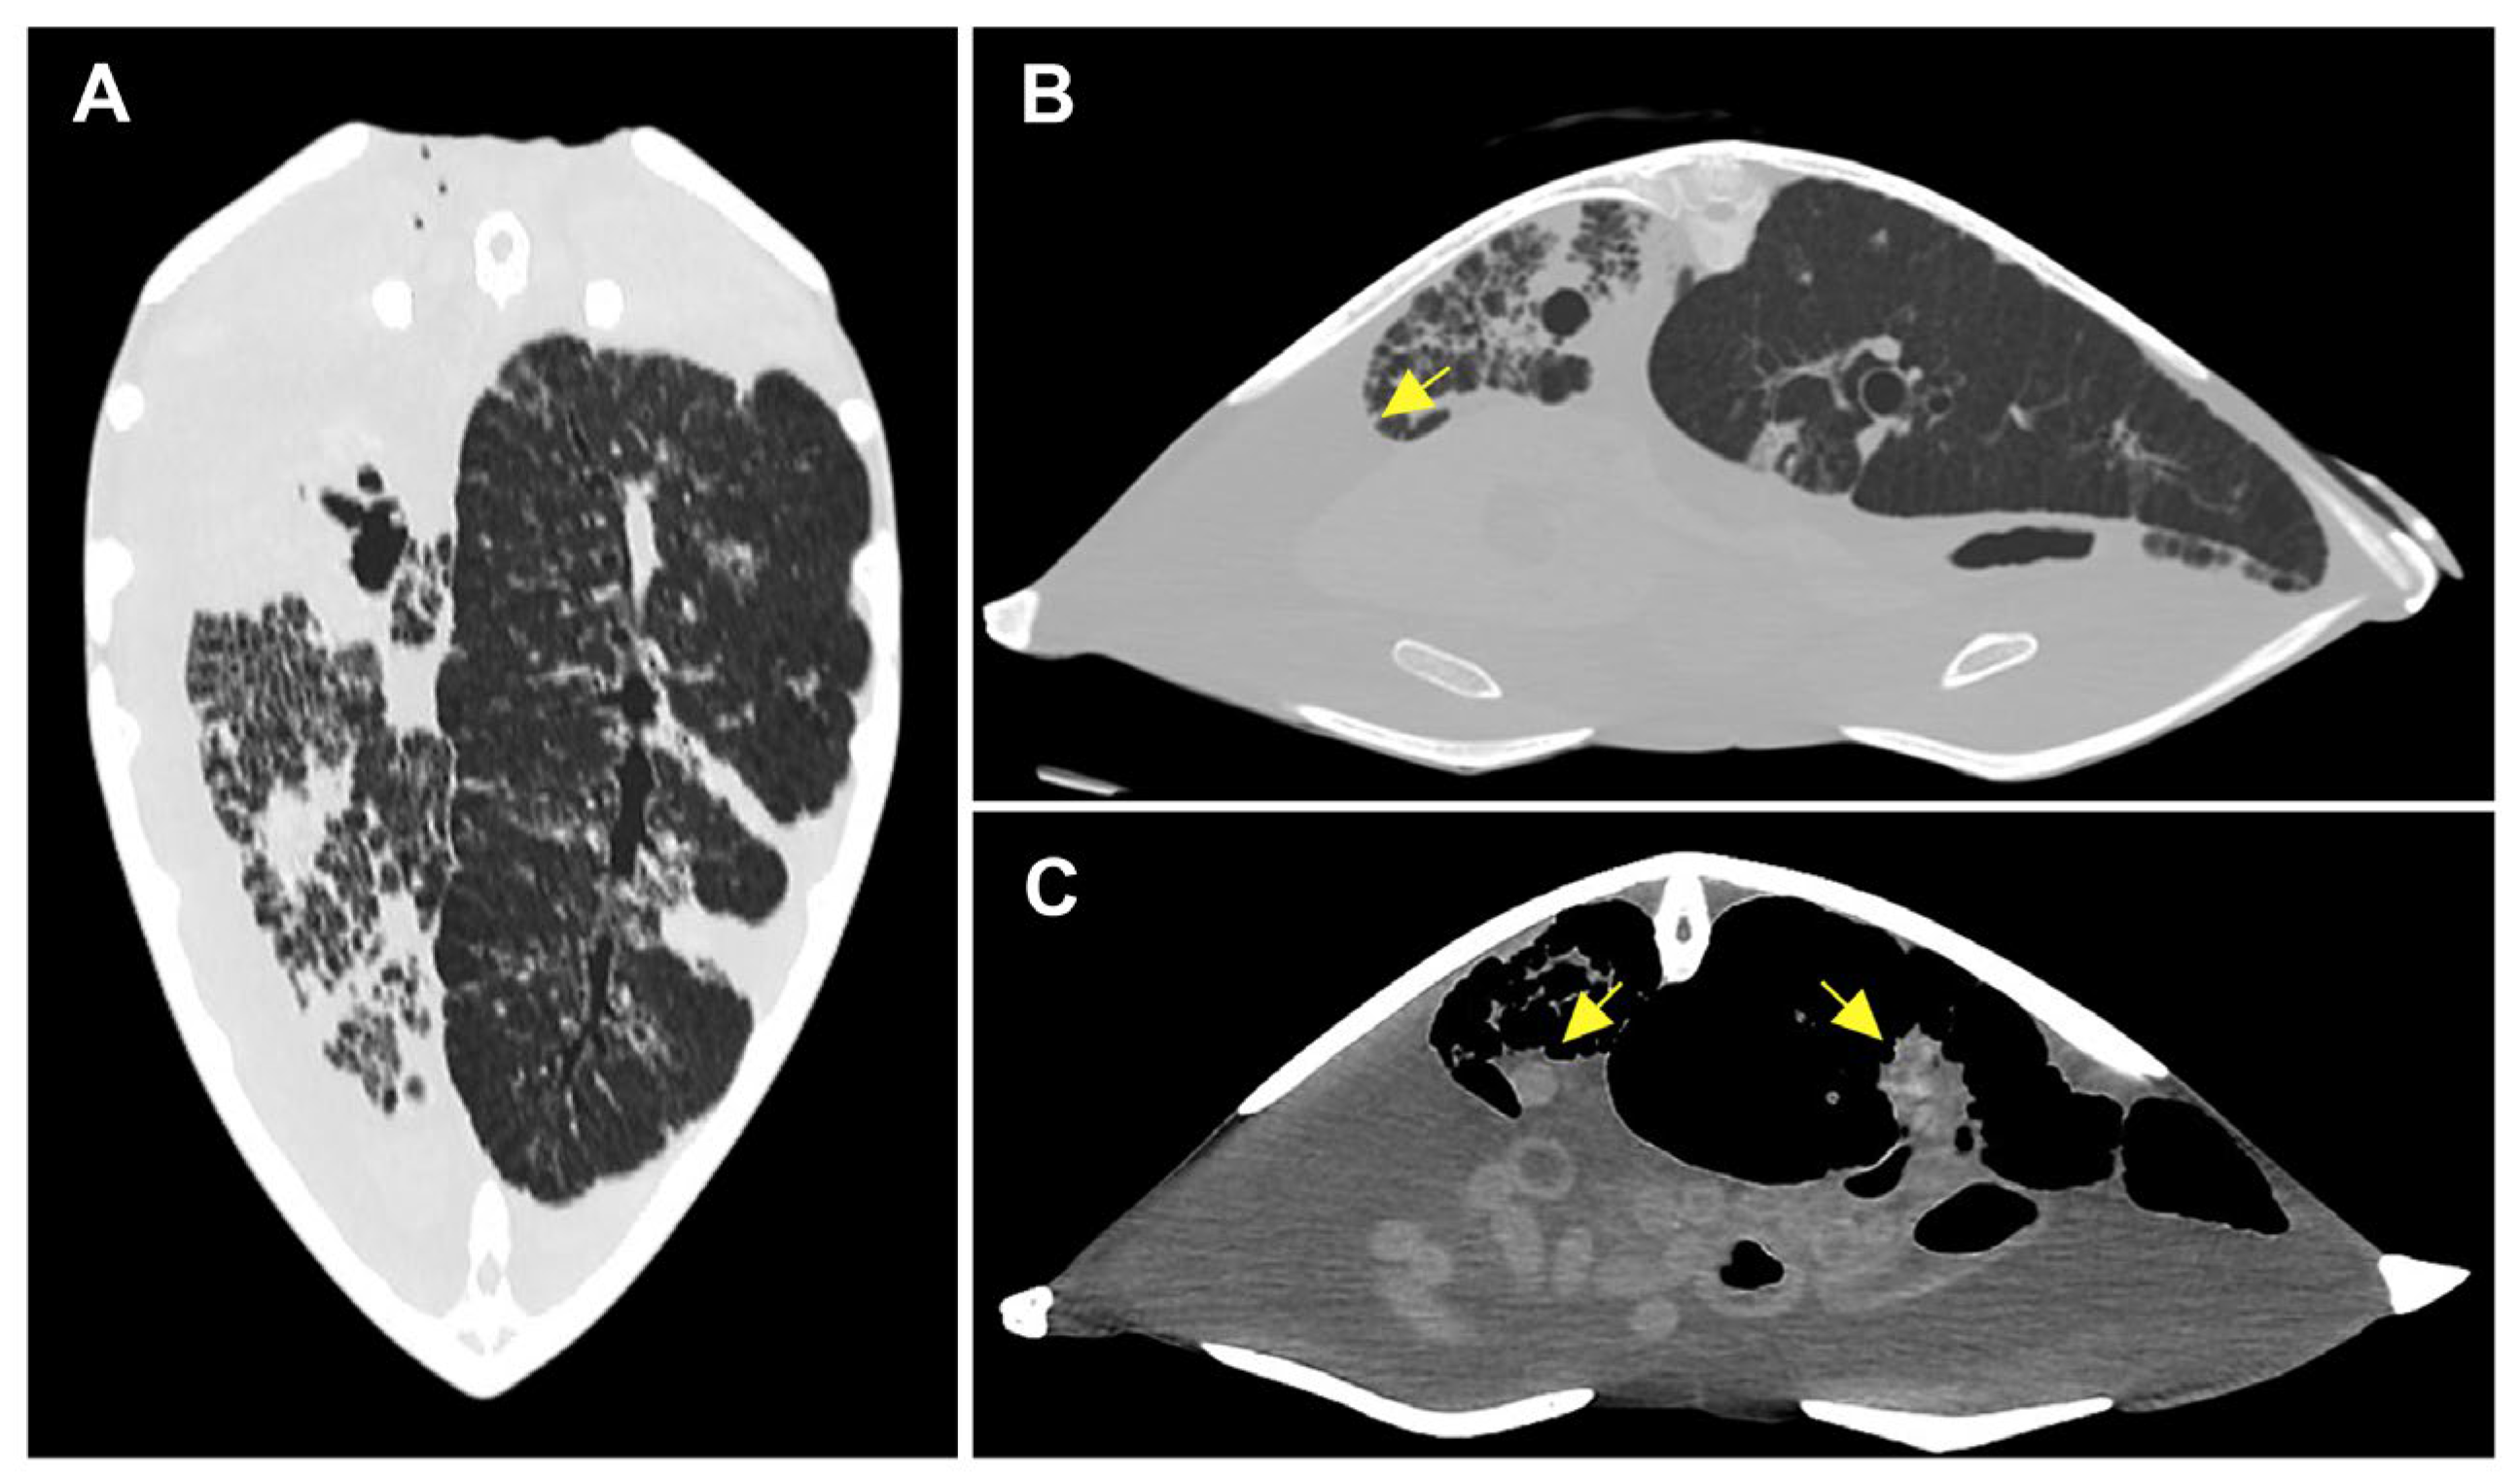

3.1.2. Radiological Findings